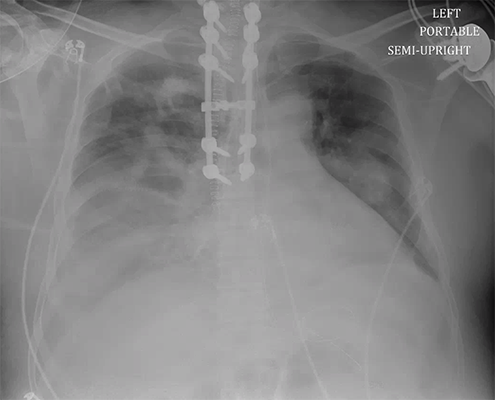

On day 3 of admission, he develops worsening hypoxemia, requiring an increase in PEEP to 10, as well as an increase in secretion burden. Based on the clinical history and the timing, with this increase in airway opacities, bacterial pneumonia (aspiration?) was of high suspicion. He was initiated on the appropriate antibiotics. At this point, with the increase in right pleural effusion on CXR, a diagnostic thoracentesis is performed-- bloody fluid is obtained. A pigtail chest tube is then placed for hemothorax, with 1L output.

CXR